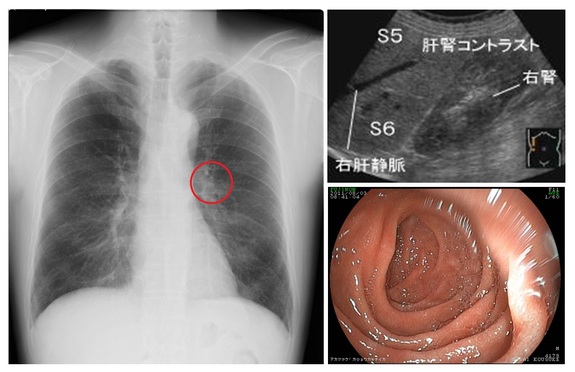

医療現場ではX線、超音波(エコー)、内視鏡などの検査画像から診断、治療を行うことが重要な手段となっていますが、検査画像から情報を読み解くことは容易ではなく熟練を要します。一方で、画像診断を行う専門医を育成するには膨大な時間と費用がかかることから、専門医が不足し、中小病院や診療所では症例に接することの少ない一般の医師が画像診断を行ったり、診療放射線技師が画像診断補助を行うことが必要になっています。

医療画像診断の学習は、実際の症例画像を見ながらそれを読み解くという訓練が最も有効なのですが、それには指導する側の労力も膨大です。そこで我々は大学病院や中核病院が保有する専門知識や豊富な経験や症例を、知的なデータベース技術を駆使して「画像診断知識ベース」や「画像症例データベース」としてデータベース化し、必要とする医療従事者がいつでもどこでも利用できるように医療画像診断eラーニング「読影指南L」として提供したいと思っています。

(医療画像の例)